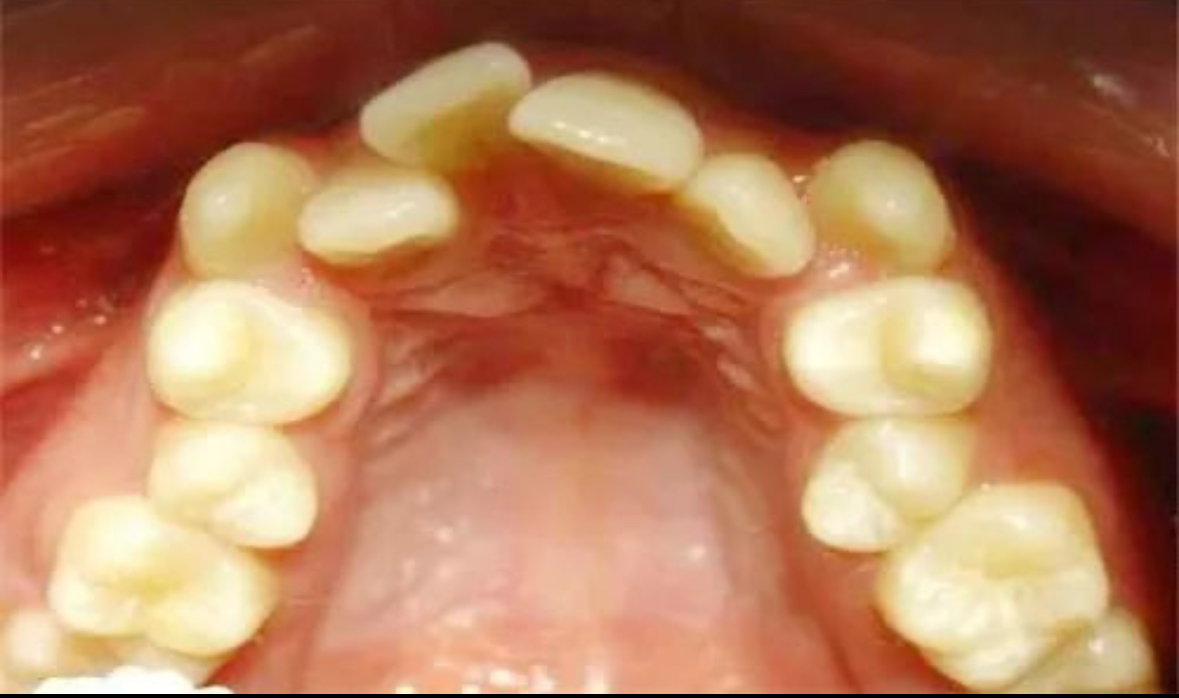

牙齒擁擠是口腔問題中的一種,指的是牙齒排列過于緊密,導致空間不足,從而影響美觀、口腔衛生和咬合功能。對于那些希望改善這一狀況的人來說,了解不同的矯正方式可以幫助他們做出更明智的選擇。珠海六和口腔醫院將介紹幾種常見的牙齒擁擠矯正方法,并探討如何根據個人情況選擇最合適的方案。

1. 傳統金屬托槽矯正

這是最常見的矯正方式之一,適用于各種不同程度的牙齒擁擠。金屬托槽通過鋼絲施加持續的壓力來移動牙齒。優點是成本相對較低且效果可靠,缺點在于外觀不太美觀,佩戴期間需要特別注意口腔衛生。

2. 陶瓷透明托槽矯正

陶瓷托槽的顏色與牙齒相近,比金屬托槽更加隱蔽,因此在視覺上更為美觀。它們同樣依賴于弓絲來調整牙齒的位置。雖然價格高于金屬托槽,但適合對外觀有一定要求的人士。

3. 隱形矯正(如Invisalign)

隱形矯正器是一種幾乎不可見的塑料牙套,可以自行摘戴,方便進食和清潔牙齒。它為患者提供了極大的舒適性和便利性,尤其適合成年人或對美觀有較高要求的人群。不過,隱形矯正可能不適用于所有類型的牙齒擁擠,具體適用性需由專業醫生評估。